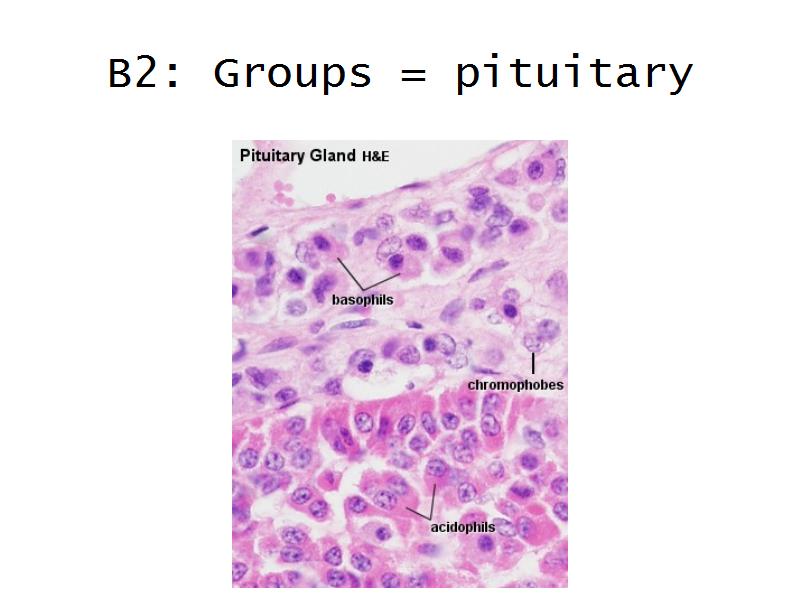

- Pituitary gland

Question B1 to B4

For each of the following 4 slides

Which gland is arranged as:

- E1: ACTH = basophils in the pituitary gland

- Slide 52: Pituitary gland

Pituitary gland